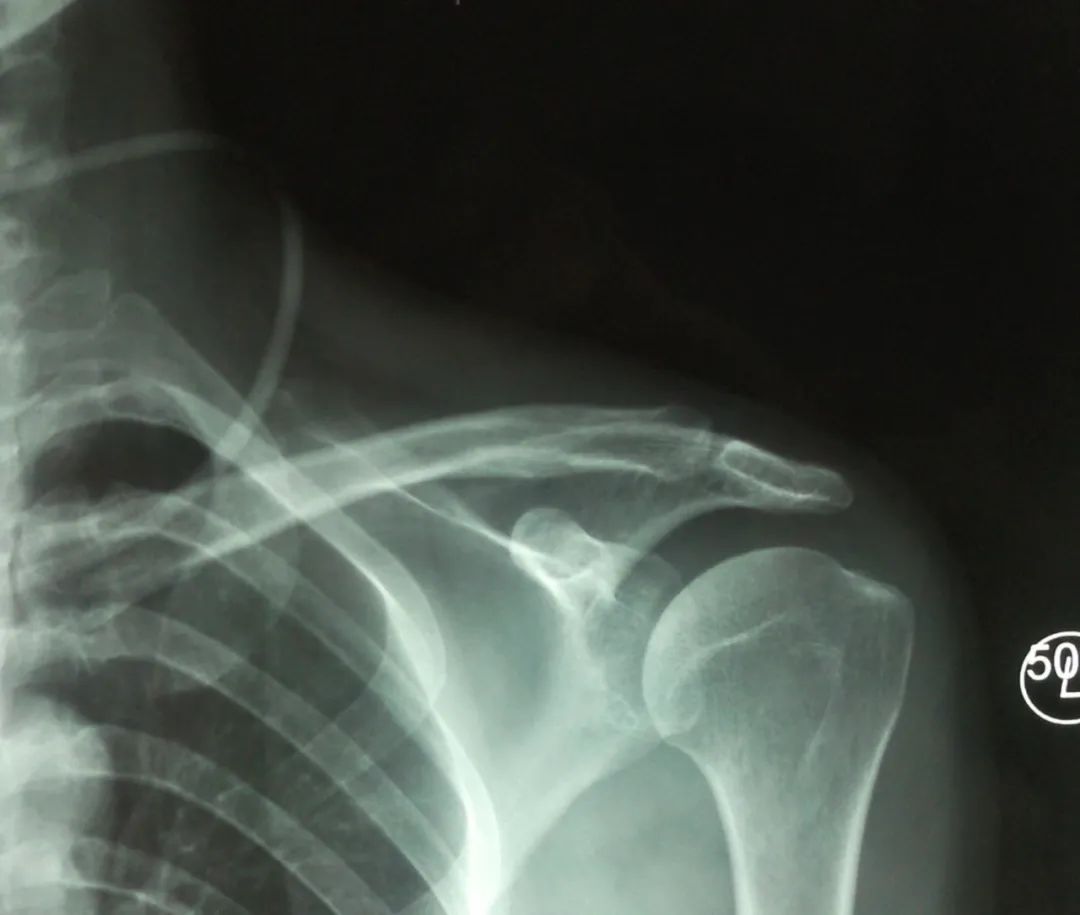

岡上肌腱

案例1:肩袖損傷